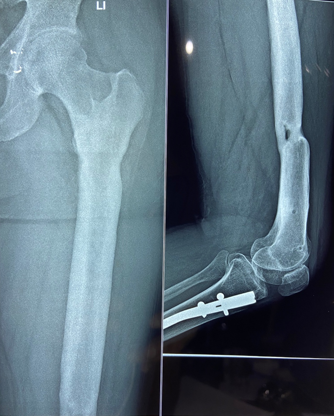

In a series of delayed union with internal fixation over 47 patients regardless of the fracture sites communition or inadequate fixation, had union in all patients including a case of infected nailing of femur. These patients had reported to Dr. S S Jha three to seven months after internal fixation at other centers. None of these patients were willing to submit themselves for further surgical intervention. Teriparatide 20mcg daily through subcutaneous route was started in all patients with adequate supplementation of vitamin D and calcium. Evident radiological bony union was perceptible after three months with clinical improvement in the initial presenting symptoms of the patients and the osseous consolidation was invariably observed radiologically within four to six months. It was only in six patients that Teriparatide was continuously used for one and half years for reasons of general debility, elderly age and osteoporosis. Radiographs of three difficult cases are being displayed from the series.

Case 1([Figure 1], [Figure 2], [Figure 3], [Figure 4], [Figure 5], [Figure 6], [Figure 7], [Figure 8], [Figure 9])

Case 2([Figure 10], [Figure 11])

- Case 1([Figure 1], [Figure 2], [Figure 3], [Figure 4], [Figure 5], [Figure 6], [Figure 7], [Figure 8], [Figure 9])

- Case 2([Figure 10], [Figure 11])